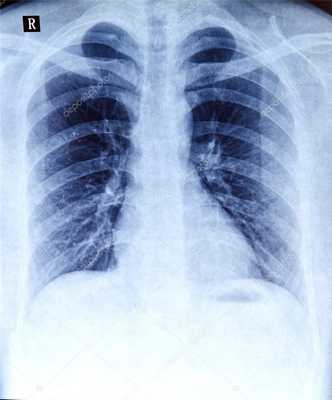

Обзорная рентгенография легких - общее рентгеновское обследование органов грудной клетки в прямой проекции. Она позволяет оценить состояние органов дыхания, сердца, диафрагмы. Является методом скриннинговой диагностики для исключения серьезных проблем с легкими и сердцем при подготовке к большим хирургическим операциям. При подозрении на какую-либо патологию назначаются дополнительные проекции для рентгеновских снимков.

Рентгенография применяется для обследования органов грудной клетки, оценки состояния лёгких, бронхов, трахеи, лимфоузлов, костей, сердечно-сосудистой системы. Современное медицинское оборудование позволяет получить четкое изображение внутренних органов в нужной проекции, что значительно упрощает и ускоряет постановку точного диагноза. Рентгенография даёт возможность выявить различные патологии, новообразования, воспаления, механические повреждения и пр.

Рентгенография легких позволяет оценить их состояние размер, форму, структуру тканей, а также расположение прочих органов грудной клетки. Для получения наиболее полной информации о состоянии лёгких, врачу необходима рентгенограмма в 2 проекциях, где чётко просматривается лёгочная ткань, купола диафрагмы, тень сердца и органов средостения, кости позвоночника, плечевого пояса, грудины. Изображение различных органов и костей наложено друг на друга.

Для корректной расшифровки изображения необходимо четкое представление о том, как на рентгенограмме выглядят здоровые органы грудной клетки. К примеру, даже малозаметные затемнения, просветления, ассиметричный легочный рисунок может свидетельствовать о серьёзном заболевании. Регулярное проведение обследований позволяет выявить патологии на ранней стадии и незамедлительно приступить к лечению.